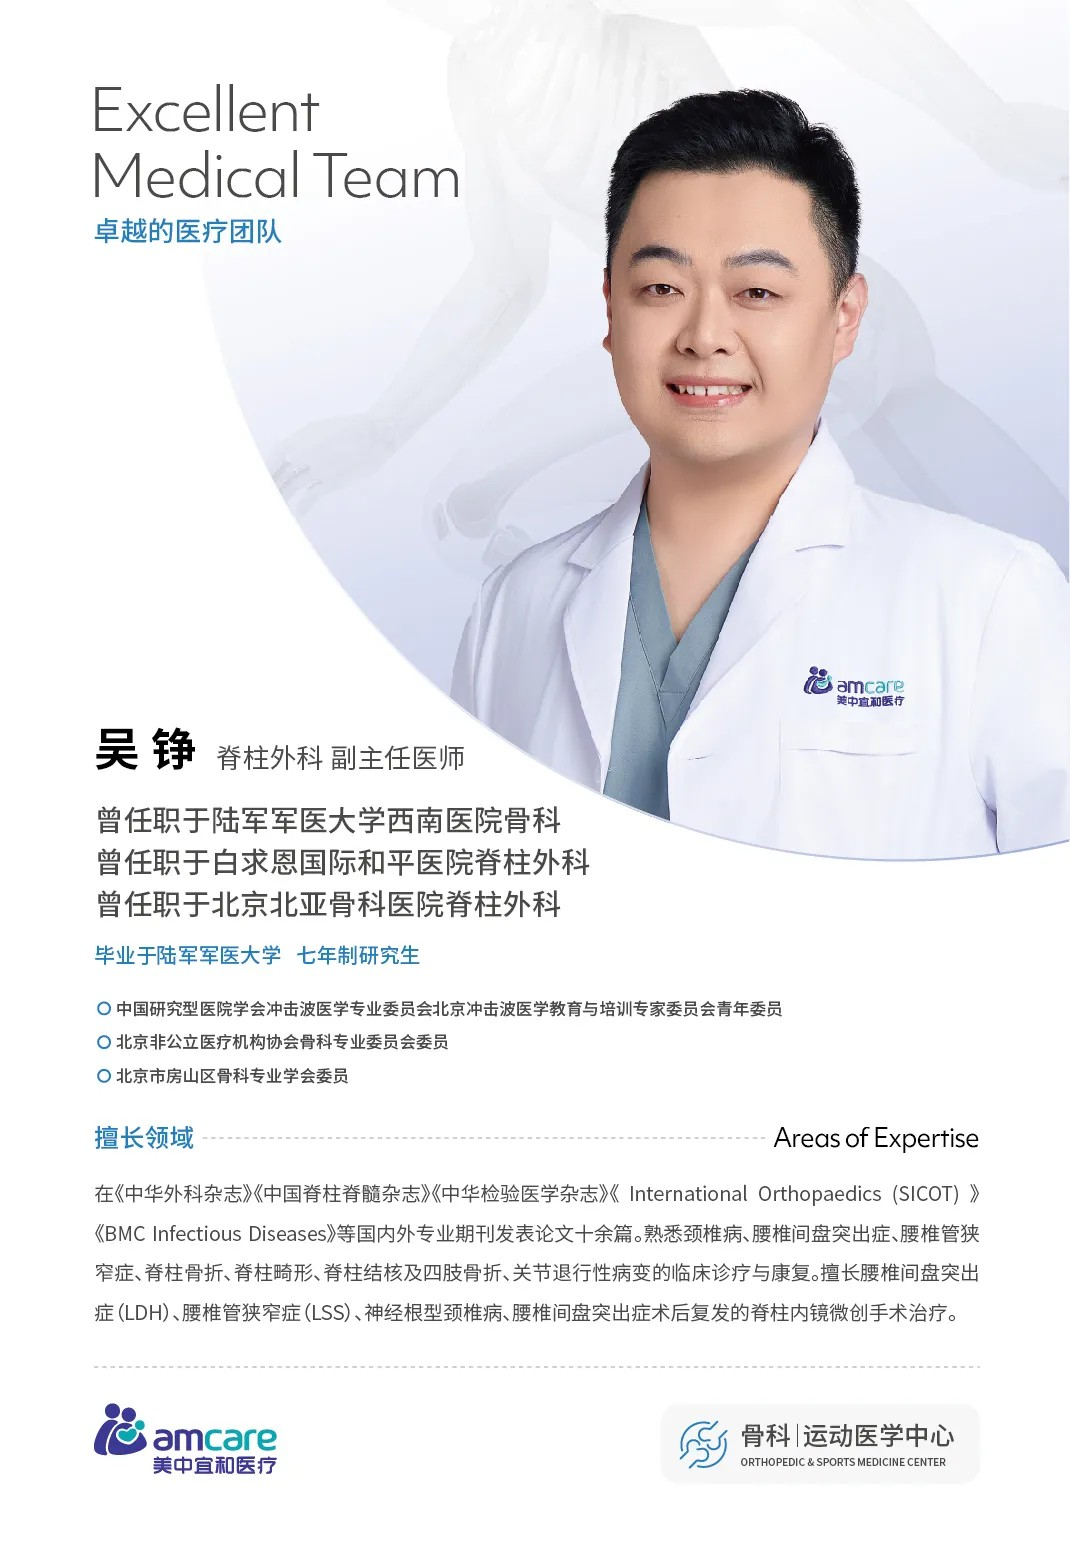

手術(shù)并非(fei) “一(yi)人(ren)之(zhi)功”,從(cong)助手精(jīng)準配(pei)郃(he)截骨、麻醉團(tuán)隊(duì)攻克氣(qi)道難題,到(dao)巡回護士協助調整體(ti)位(如擡肩膀、撤腹部(bu)體(ti)位墊),每箇(ge)環節(jie)都需專(zhuan)業默契。

專(zhuan)業審稿醫(yī)生(sheng)

診療範圍

足踝疾病 下肢矯形 膝髋疾病

脊柱疾病 關節(jie)疾病 運動(dòng)醫(yī)學(xué)